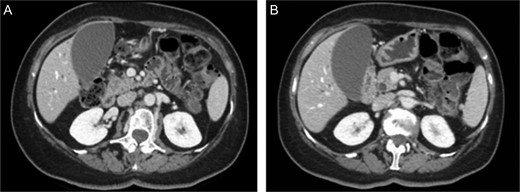

First the abdominal ultra sonography (AUS) and then CT scan revealed the presence of well-defined hypodense pancreatic head mass of 2 cm of diameter, determining bile duct and Wirsung’s duct dilatation; mesenteric vessels were clearly free of infiltration, no liver or lung suspected lesions were detected as well as volume increased lymph nodes (Fig. 1). Ecoendoscopic ultra sonography (EUS) confirmed the presence of a hypoechoic and well-defined pancreatic head mass (18 × 15 mm) and without sign of vessels infiltration (Fig. 2). A fine-needle aspiration (FNA) was performed and histopathological examination showed the presence of neoplastic cells with morphological features like the lung ones and consistent with metastasis from primary adamantinoma.

MDCT scan. (A) CT scan with well-defined hypodense pancreatic head mass of 2 cm of diameter after contrast medium intravenous injection. (B) CT scan which highlight bile duct dilatation.